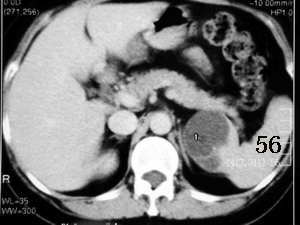

经过认真观察图片,发现刚才搞错了,病变应该位于脾脏,而且未见强化,边缘清晰,如果没有猜错的话应该是:脾脏囊肿。

应该为脾脏来源的,囊性肿瘤,从前后ct片显示,有轻度强化改变(ct值),但好像有快速消退的感觉???

mr示脾内缘类圆形长t1长t2信号影,边界清楚

ct示脾内缘囊性低密度影,强化后其边缘实质部分与脾同步,且强化程度一样,

考虑脾囊肿

脾脏来源的,低密度,边界清,有分隔,有强化。

考虑:脾脏血管内皮瘤。

考虑肾上腺嗜铬细胞瘤囊变可能性大,病灶呈囊实性,边界清楚,结节强化。

左侧肾上腺受压,病变不是来源于肾上腺,mri脂肪抑制病变为高信号,除外脂肪瘤,考虑来源于脾脏可能性大,强化后壁与脾脏强化基本相似,其内见分隔,囊腺瘤,血管瘤不除外。

cor上显示病灶与肾上腺无关,stir仍呈高信号,增强ct扫描各期均为低密度,且感觉张力较高,还是符合脾脏囊肿性病变的表现。

首先病灶的部位位于脾脏,这一点应该可以达成共识,因为它相邻的实质部分与脾脏同期.同时强化,并可见“鸟嘴”征象。第2:囊性病灶没有明显强化,在延期扫描的时候也是一样。也无病灶缩小的特征。所以我感觉应该考虑:脾脏囊性占位(脾脏囊肿可能性大)

同意大多数同仁意见,关键在于+c上明显显示脾动脉一分支走向囊肿边缘,同时与肾上腺无关.